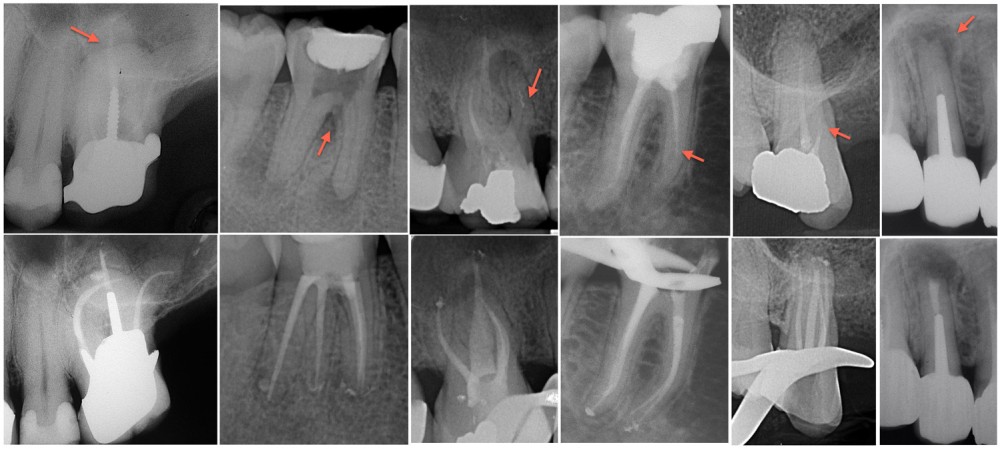

La décision est prise selon le contexte clinique et les attentes du patient. L’étanchéité coronaire est évaluée, même si son appréciation reste subjective. De même, le projet prothétique futur entre en jeu. L’accès au réseau endodontique sera plus ou moins facile. Il est d’ailleurs tout à fait possible d’envisager un passage à travers l’élément prothétique. L’anatomie canalaire complexe et la présence d’obstacles (fragments, calcifications…) peuvent être des indications d’abord chirurgical.

La chirurgie endodontique ne se limite pas à couper la racine mais consiste en un traitement endodontiquea retro. Comme pour le retraitement par voie orthograde, l’intervention peut intéresser un ou plusieurs canaux. L’imagerie est l’élément clé de la décision. Le CBCT (Cone Beam Computed Tomography) vient au service du sens clinique du praticien.